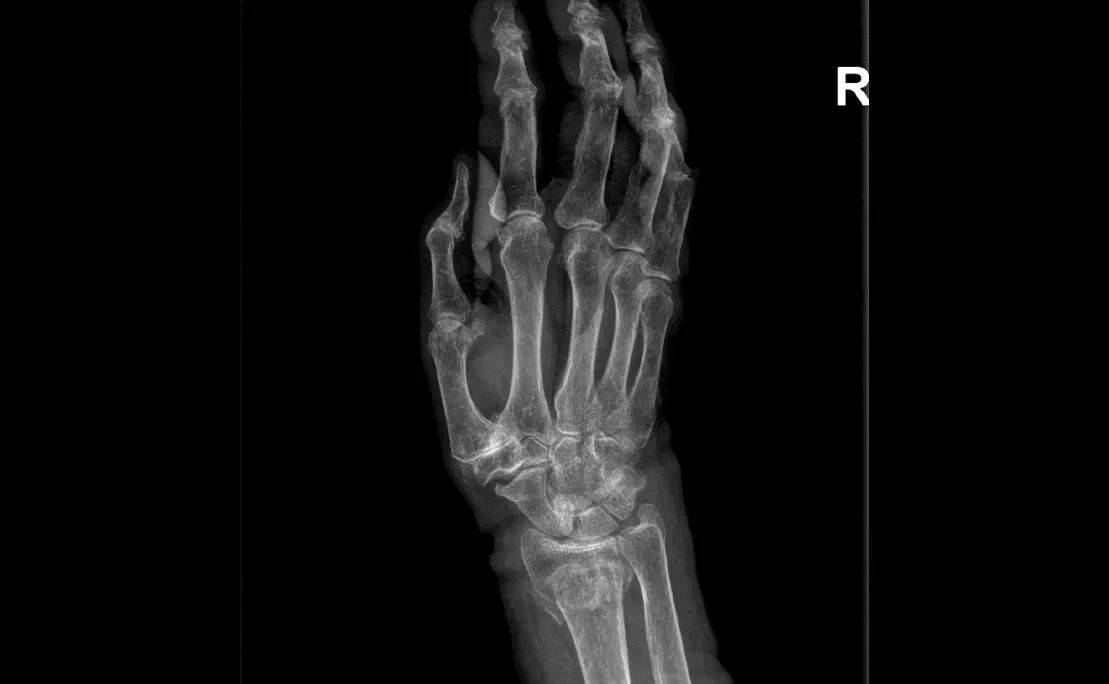

Polsartrose & Pisiformetriquetrale artrose

Wat is het?

Polsartrose is slijtage van het kraakbeen in één of meerdere polsgewrichten. Dit kan ontstaan in het:

- Radiocarpale gewricht (hand–pols)

- Midcarpale gewrichten

- Pisiforme–triquetrum gewricht

- DRUJ (spaakbeen–ellepijp)

Oorzaken zijn vaak: doorgemaakte breuken of ligamentletsels, doorgemaakte infectie, reumatische aandoeningen.

Klachten

- Pijn, vooral bij bewegen of belasten

- Zwelling en roodheid van betrokken gewricht

- Stijfheid

- Verminderde kracht

- Scaphoidectomie + four-corner fusieHet scaphoid wordt verwijderd, vier polsbeentjes worden vastgezetOngeveer 45% beweeglijkheid en 80% kracht blijft behouden

- Proximale rij carpectomieVerwijderen van scaphoid, lunatum en triquetrumNieuwe scharnierfunctie tussen capitatum en onderarmResultaten vergelijkbaar met four-corner fusieSoms aangevuld met een resurfacing-prothese

- Totale polsartrodeseHele pols wordt vastgezetVingers kunnen wel nog bewegenGeschikt voor zwaar belastend werk

- PolsprotheseVervanging van het polsgewrichtBewegingsbeperking blijft, maar voldoende voor dagelijkse activiteitenBelasting moet beperkt blijven om vroegtijdige slijtage te voorkomen

- DRUJ-protheseVervanging van alleen het draai-gewricht tussen spaakbeen en ellepijp

- PisiformectomieVerwijderen van het os pisiforme bij pijn in dit kleine gewrichtGeen verlies van polsfunctie